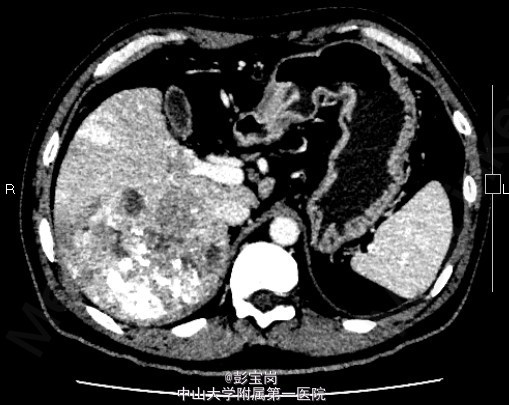

男性,42岁;因“肝癌行TACE术后,拟行手术治疗”入院。患者1月前体检发现原发性肝癌,于25天前在外院行肝动脉栓塞化疗(TACE)术。2天前患者就诊我院,查上腹CT示:右肝后叶多发结节或肿块,碘油栓塞后改变,病灶内和周边部仍有血供,门脉右后下支癌栓形成。现为进一步诊治门诊拟“肝细胞癌”收住我科。起病以来,精神食欲可,大小便通畅,体重无明显变化。既往史肾结石病史,否认肝炎病史。

查体无特殊; 检验:白细胞WBC:13.27;血红蛋白Hb:121g/L;血小板PLT:225x10^9/L;肿瘤标记物:甲胎蛋白(AFP)111.32 ug/L;癌胚抗原(CEA)9.40 ug/L;CA125 20.2 U/mL;CA19-9 11.04 U/L;HBsAg(+)

诊断:肝细胞癌 处理:右半肝切除术、胆囊切除术、腹腔粘连松解、膈肌部分切除修补、门静脉切除取癌栓、右侧肾上腺转移瘤切除